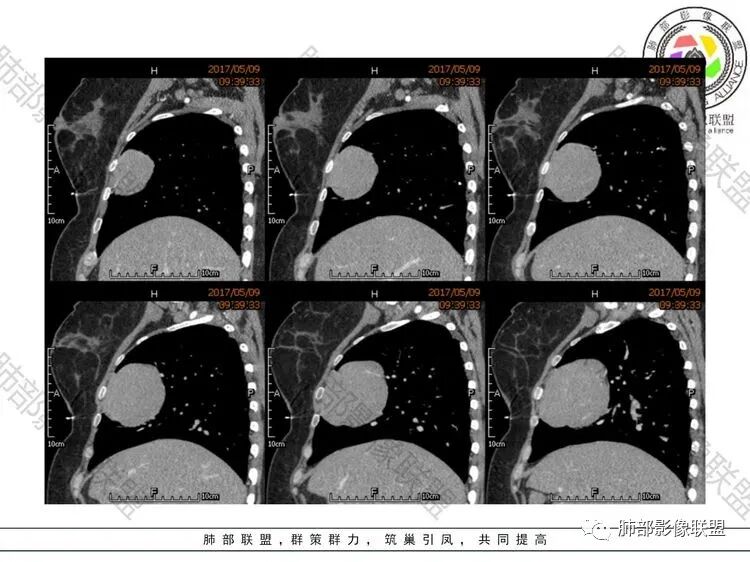

中年女性,体检发现,纵隔前外侧见不规则肿块,内见散在钙化灶,主动脉及心脏受压向后内侧轻度移位,增强后呈均匀性强化,未见明显坏死区,肺动脉延伸其中,轮廓光滑,肿块前外侧见胸膜尾。考虑胸膜来源可能性大,SFT?鉴别胸腺瘤

主要定位,胸膜来源,与纵隔脂肪间隙可见,sft。如果定位纵隔,考虑胸腺瘤。

晨读:定位前纵隔偏右侧,病变向右侧突出,形态欠规则,与肺组织交界清楚,右肺受压体积缩小,平扫密度不均匀,可见高密度钙化,增强后可见条状强化,51岁,考虑胸腺瘤囊变,囊性畸胎瘤,鞘瘤囊变

晨读:中年女性,体检发现病变。胸部CT:纵隔右前外侧不规则肿块,内乳动脉供血、胸膜掀起,肺动脉似乎也伸入其中?主动脉及心包受压向内后侧移位,肿块分叶、内见明显分隔、散在点状钙化灶,增强后呈均匀性强化。左侧膈顶有抬高?考虑:胸腺瘤(还是选B2吧)?鉴别SFT、神经源性肿瘤、淋巴瘤等。

晨读:女,51岁,体检发现纵隔占位。CT示右前纵隔软组织肿块,密度较均匀,内乳动脉及临近大血管受压移位,边界清晰,内部可见点状钙化,增强扫描轻度均匀强化,内部可见血管穿行,考虑纵隔来源,胸腺瘤可能,鉴别SFT

晨读:51岁女性,前纵隔偏右侧占位,分叶?密度比较均匀,肿块内部见斑点状的钙化影,增强均匀强化,体动脉供血?从年龄看排除生殖细胞肿瘤,未见明显脂肪成分,基本排除畸胎瘤,首先考虑胸腺瘤。鉴别淋巴瘤。

晨读:老年女性,右前纵隔分叶状软组织密度肿块影,内有斑点状钙化,周围脂肪间隙清晰,增强轻度均匀强化,可见线样血管穿行影。常规考虑胸腺瘤(AB型),鉴别淋巴瘤、SFT。

前纵膈偏右侧肿块,分叶,边缘清晰,内可见多发斑点状钙化,强化均匀,血管穿行,考虑胸腺瘤AB型,鉴别SFT。